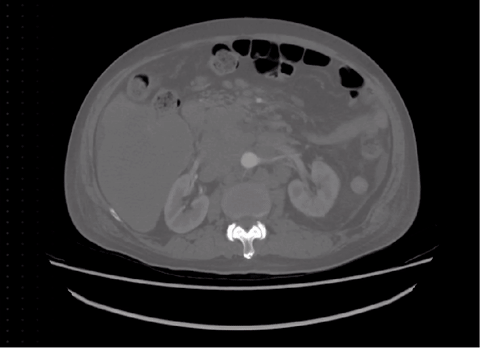

图1 COSMOS 553K涵盖了大多数医学影像模态和生物医学领域分割目标。例如,脑肿瘤、眼底血管、甲状腺结节、脊柱、肺、心脏、腹部器官或肿瘤、细胞、息肉和手术仪器等。人体图像来自Freepik,作者为brgfx(网址https://www.freepik.com/free-vector/anatomical-structure-human-body 27539420.htm)。

图7 典型的SAM良好案例。

图8 典型的SAM失败案例。